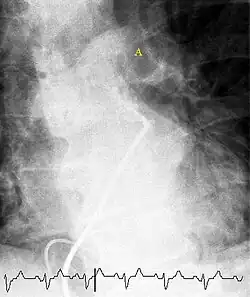

(A) After inhalation of 20 mCi of Xenon-133 gas, scintigraphic images were obtained in the posterior projection, showing uniform ventilation to lungs.

(B) After intravenous injection of 4 mCi of Technetium-99m-labeled albumin, scintigraphic images shown here in the posterior projection. This and other views showed decreased activity in multiple regions.

A ventilation/perfusion scan (or V/Q scan or lung scintigraphy) shows that some areas of the lung are being ventilated but not perfused with blood (due to obstruction by a clot).[17] This type of examination is as accurate as multislice CT, but is less used, due to the greater availability of CT technology. It is particularly useful in people who have an allergy to iodinated contrast, impaired kidney function, or are pregnant (due to its lower radiation exposure as compared to CT).[57][58][59] The test can be performed with planar two-dimensional imaging, or single photon emission tomography (SPECT) which enables three-dimensional imaging.[50] Hybrid devices combining SPECT and CT (SPECT/CT) further enable anatomic characterization of any abnormality.